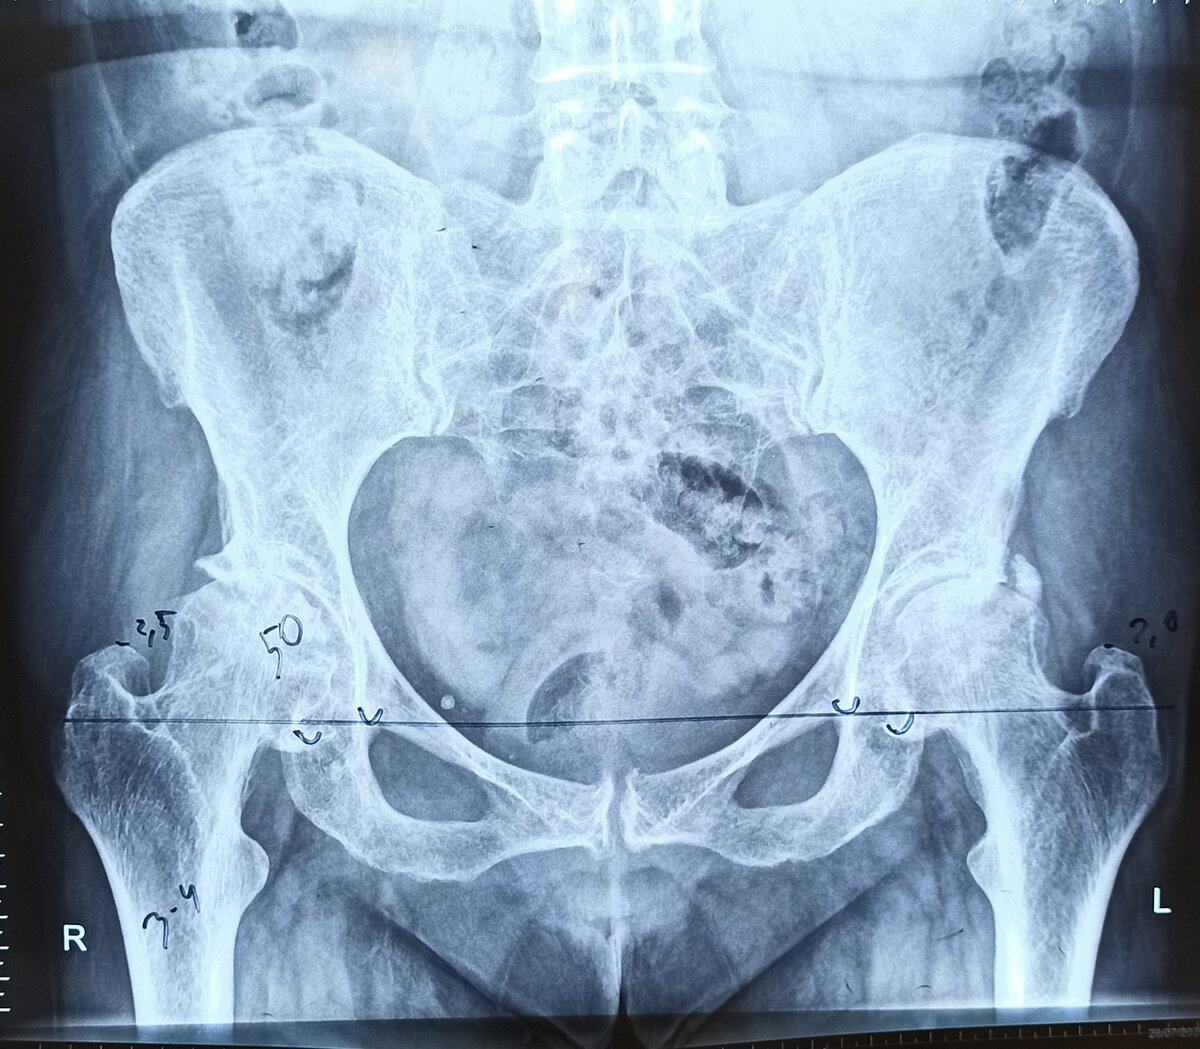

Многим ортопедам и не многим пациентам знаком такой диагноз как асептический некроз кости. Заболевание встречается в любых областях скелета, и может протекать бессимптомно до тех пор, пока не будет поражен сустав. Асептический некроз головки бедренной кости (АНГБК) имеет значительную медико-социальную проблему, чаще всего он поражает молодое работоспособное население. Истинную этиологию данного заболевания по сей день установить не удается, так как она складывается из множества факторов. Но одной из частых причин является применение глюкокортикостероидов, которые вызывают апоптоз или саморазрушение остеобластов и остеоцитов (основных структурных единиц кости). При первых проявлениях боли после перенесенного COVID-19 и лечения глюкокортикостероидами необходимо пройти обследование опорно-двигательного аппарата для исключения возможных отдаленных осложнений.